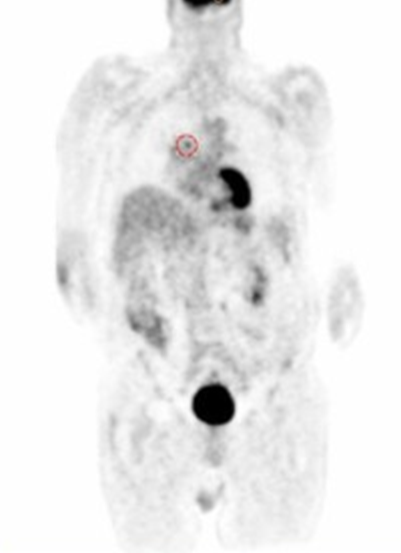

what are the two different lymphoma

Hodgkin’s (HL) and non-Hodgkin’s lymphomas (NHL

how can PET be used for lymphoma

staging of the disease

how are pre and post therapy scan helpful for lymphoma

evaluating response to therapy

the image on the left is pre or post therapy for lymphoma

pre therapy

the image on the right is pre or post therapy for lymphoma

post therapy